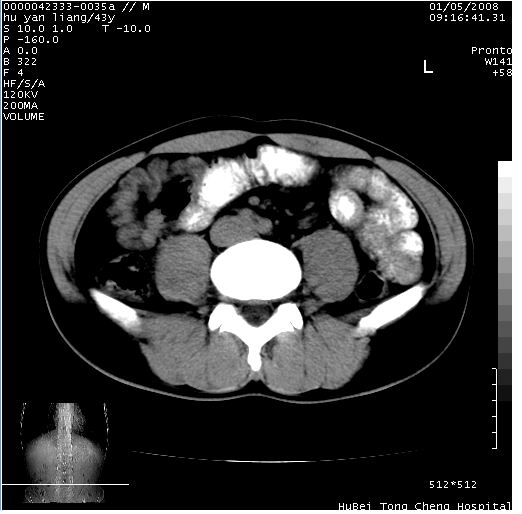

患者 男,43岁。右上腹不适1年余。既往有“肝右叶肝脓肿”病史,经保守治疗后痊愈。

b超提示:1)肝右叶肝内胆管结石。2)肝右叶占位性病变待排。

上中腹部ct轴位平扫+增强扫描(层厚10mm,螺距1.0,重建间隔10mm),图像如下:

肝右上叶偏后方较大团片状钙化灶,支持:肝脓肿后遗改变!

肝右叶后段团块状钙化灶,结合病史考虑肝脓肿痊愈后表现。